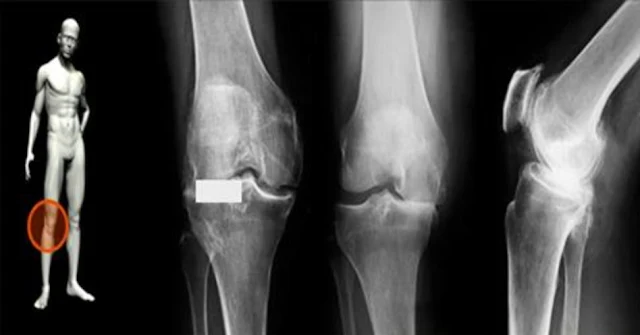

Хрящ – это соединительная ткань, которая покрывает и защищает суставную поверхность кости. Он является частью многих других костных структур человека, как нос, бронхи, уши, грудь, позвоночник, локти, колени и бедра.

Старение и дегенеративные заболевания, такие как остеоартроз, приводят к проблемам с хрящом и поражают суставы плеч, шеи (затрудняет движения головы и вызывает головокружение), бедер, колен, рук и ног.

Есть несколько признаков, указывающих на повреждение хряща: боль при движениях, отеки и напряжение мышц.